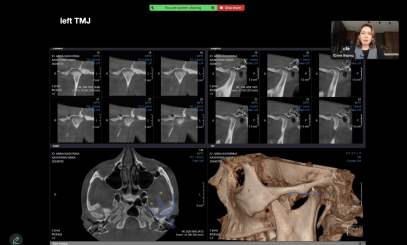

МРТ+Кондилография

Компрессия ВНЧС

Анатомия. Связь окклюзии и ВНЧС